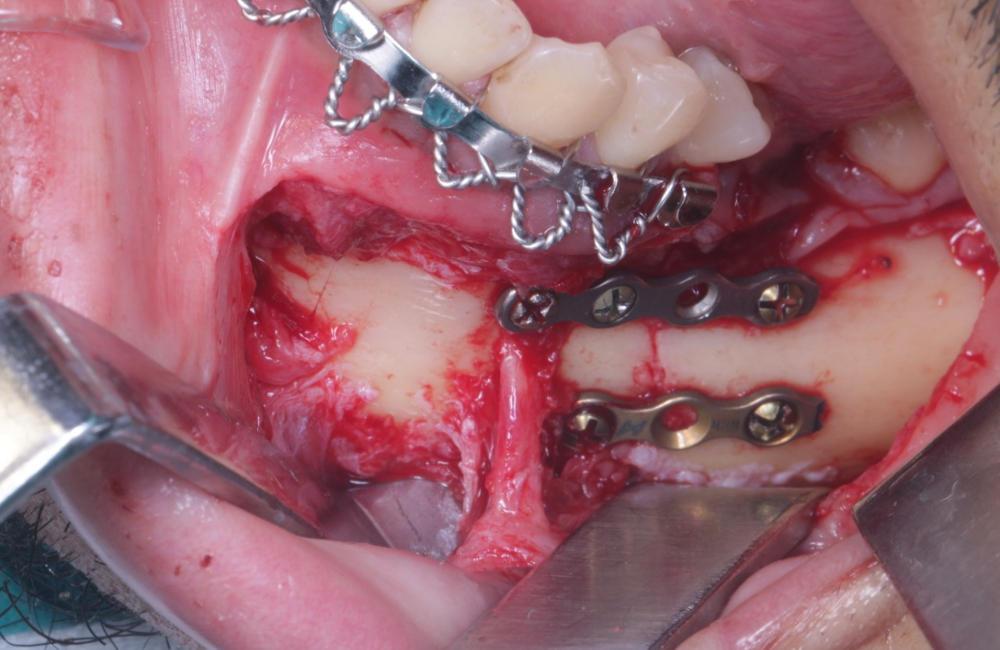

Corrección de fractura mandibular

TRATAMIENTO

REALIZADO

• Cirugía Oral

antes Corrección de fractura mandibular despues Corrección de fractura mandibular